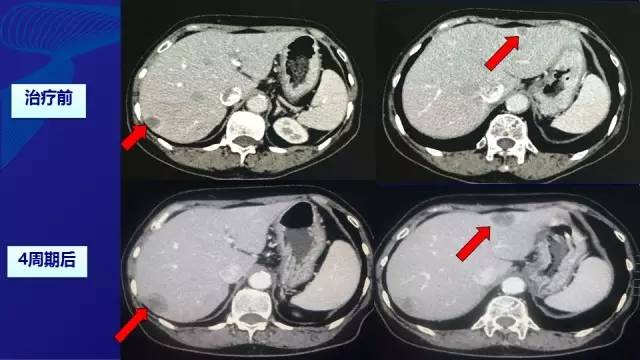

● 因为经济原因拒绝使用靶向药物,予XELOX方案化疗(减量) –奥沙利铂:100 mg/m2, d1 –卡培他滨:850 mg/m2,BID, d1-d14。无严重不良反应。

● 2周期—SD; 4周期—PD